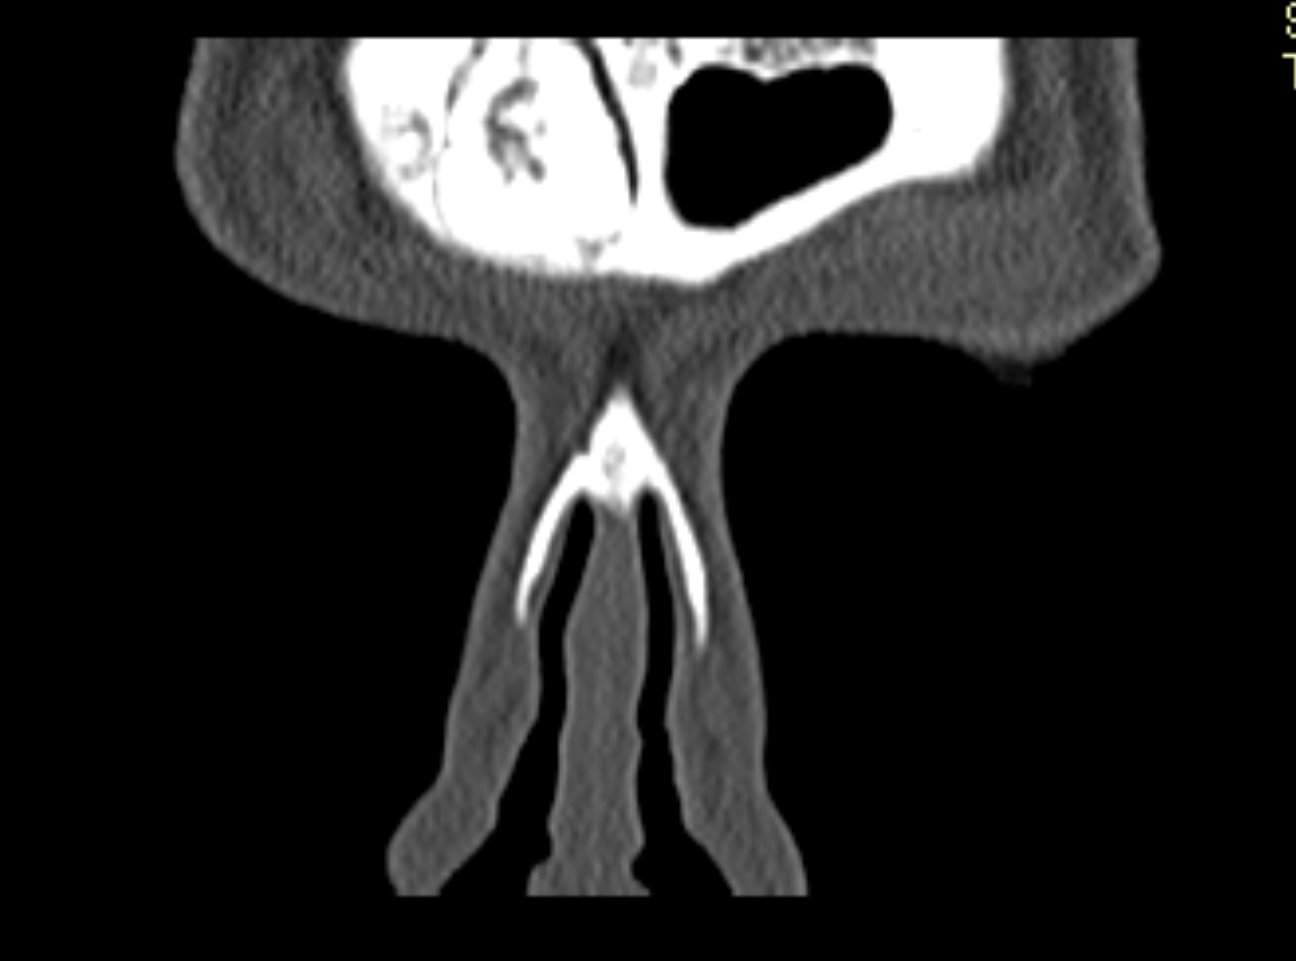

Ziua 1 postoperator, pacienta efectuează CT sinusuri paranazale de control care certifică ablația completă a formațiunii.